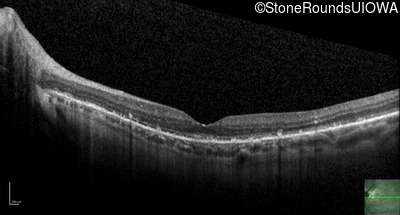

Optical Coherence Tomography - Left - 20/25 +3

Exemplar / OCT Stack